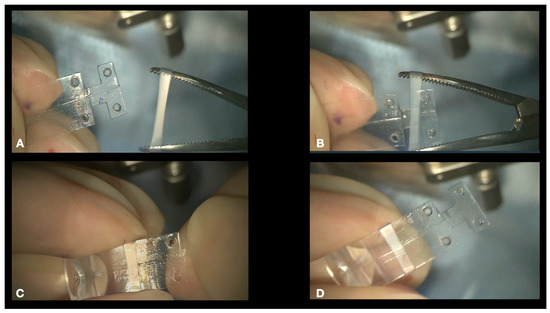

- Connecting the NPB on the NPD Loading device. We suggest connecting the NPB to the NPB loading device (Figure 6). As an alternative, the NPB can be held with bayoneted forceps, but attention should be taken not to break the NPB. To connect the NPB to the NPB loading device, it is necessary to execute the following steps:

- Hold the handle of the NPB loading device.

- Align the tip of the loading device to the external side of the NPB arm.

- Insert the tip of the loading device into the silicone sleeve with the help of non-toothed forceps.

- Connect the teeth of the loading device, embracing the NPB anterior wings.

- Disconnecting the NPB Loading Device From the NPB. If the NPB loading device was used, at the end of the procedure, it must be carefully disconnected from the NPB. We advise to keep the NPB’s most anterior wing steady with non-toothed forceps and to gently elevate it by 1mm and pull the NPB loading device out.